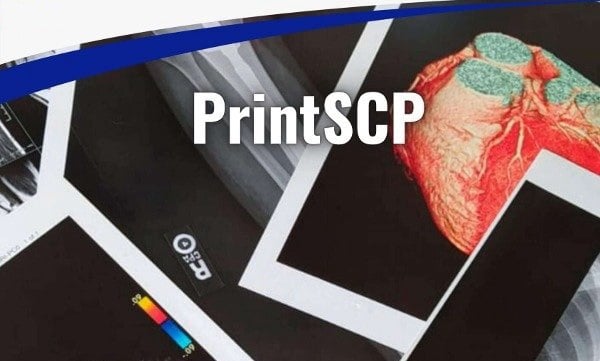

DICOM PrintSCP / CD/DVD/USB Burning Software

We specialize in developing reliable medical imaging solutions tailored to the daily operational needs of radiology departments, diagnostic centers, and healthcare facilities.

We have successfully developed two specialized healthcare software solutions:

◆ PrintSCP Software for seamless printing of medical images from PACS.

◆ CD/DVD/USB Burner Software for burning and distribution of patient imaging studies.

Whether enabling fast and accurate DICOM image printing or ensuring compliant and efficient image sharing via physical media, our solutions are designed to integrate smoothly into existing workflows, enhance efficiency, and support clinical decision-making with precision and reliability.

Solutions

- DICOM PrintSCP.

- DICOM Burner.

- Custom Software.

Services

- Consultancy.

- UI Design.

- Development.

Tech Stacks

- Python.

- PHP Core.

- DotNet Core.